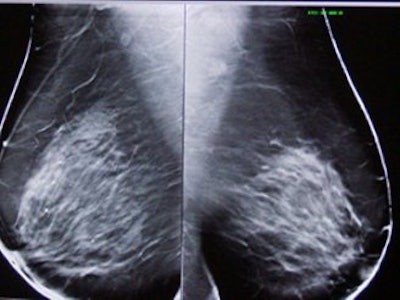

| Left, conventional full-field digital mammogram (FFDM). Right, DBT exam. All images courtesy of Dr. Daniel Kopans, senior radiologist at Massachusetts General Hospital, and Richard Moore, director of Kopans' breast imaging research projects. |